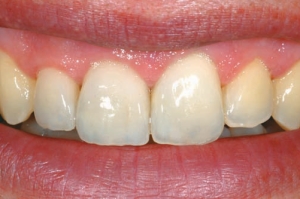

Figure 4--The patient's smile. Esthetics has been restored, in harmony with surrounding teeth, even if not in symmetry.

Wake up, look at yourself in the mirror, smile and love what you see! Is there a better way to start your day? The perception of beauty starts in our eyes and goes to our soul with a process involving feelings, knowledge and experiences. The smile is responsible for 60 up to 70% of the … Read more